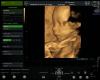

Второй скрининг прошла. Все хорошо с малышкой ❤️

Хочется сходить на 3д узи. Вы на каком сроке ходили?

Первый раз включали как раз на втором скрининге, я даже не знала, что это в него входит. Потом делали в 28 недель, был самый классный период — четко и даже похоже.

Несколько раз 3д подключали в 34 и 37, но там человек уже большой и не всегда попадал в кадр :))

Мне вчера узист сказал 27-29 оптимально

Ходила 28-29 недель)

Говорят что самый хороший обзор в 30 недель , еще не ходила но пойду ближе к 30